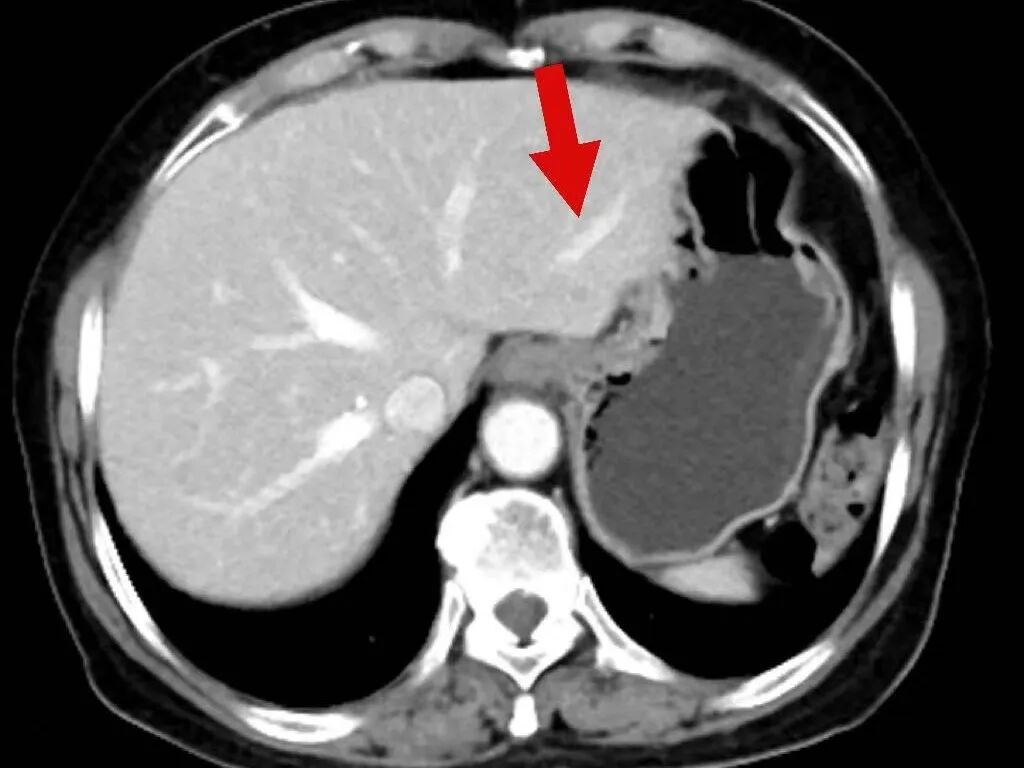

2025年3月17日,肿瘤诊疗中心团队首次为毕女士成功实施BACE治疗。术后患者病情暂时稳定,但5月10日复查显示肺部原发病灶稳定,肝脏转移病灶再次增大。

面对病情反复,团队没有放弃,果断升级治疗方案,决定同期施行BACE联合肝动脉化疗栓塞术,继续强化局部控制。“对于这类晚期患者,局部介入的优势在于能够高效、低毒地控制关键病灶。”介入医学科主任杨亚平说,“BACE联合肝动脉栓塞这类技术既能提高肿瘤部位的药物浓度,又减少了全身副作用,为后续治疗创造了条件。”

令人鼓舞的是,治疗一个月后复查显示,毕女士肺部和肝脏的肿瘤明显缩小,病情得到有效控制,生活质量显著改善。出院时,毕女士激动地说:“本来以为病情已经没希望了,是中山医院的专家们没放弃我,一次次调整方案,现在我不仅不怎么难受了,还能正常生活,真的太感谢他们了!

在玉溪市中山医院肿瘤诊疗中心治疗后,肿瘤在明显缩小